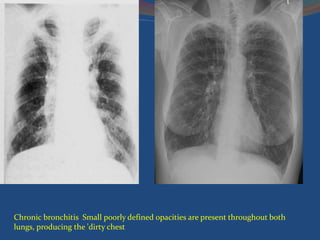

Chronic bronchitis Small poorly defined opacities are present throughout both

lungs, producing the 'dirty chest

Chronic bronchitis Smallpoorly defined opacities are present throughout both lungs, producing the 'dirty chest